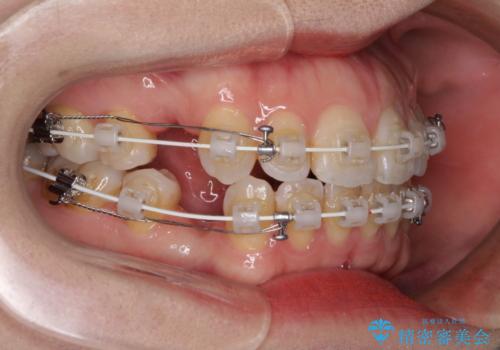

- 矯正装置

- 審美装置

- 唇の閉じにくさを気にして来院された患者様です。

上下左右第一小臼歯4本を抜歯し、ワイヤー装置にて口元を引っ込めるよう矯正治療を行うこととしました。